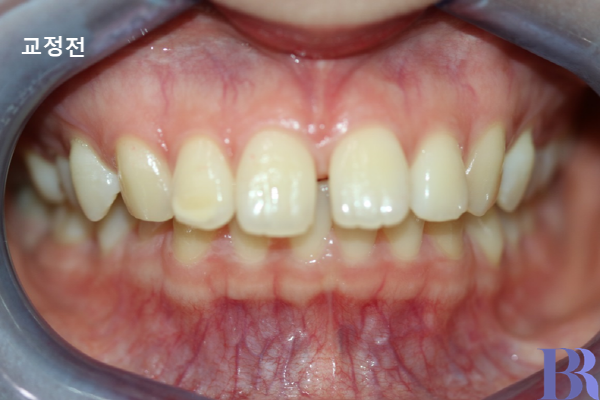

윗니가 아랫니에 비해 앞으로 많이 나와있다.

입술돌출 정도는 중간 정도

Case.

"입이 살짝 나와보이고,

치아 사이 공간이 있어요."

- 증상 : 치아사이 공간 있고 과개교합 존재

과개교합 : 윗니가 아랫니를 깊게 덮음.

그로 인해 위에 앞니 사이에 공간이 발생함.

발치교정 사례 : 윗니와 아랫니 앞뒤 차이가 심하게 나네요.

발치교정 : 하악 교정전 모습